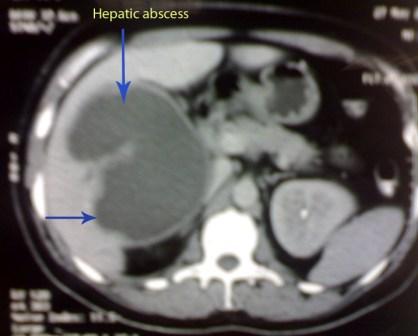

A 35 years old, male, developed fever and generalized bony aches, so he sought medical advise, received antibiotics and symptomatic treatment for one week but the condition sustained. So he was admitted to the fever hospital, diagnosed typhoid fever, received treatment, antipyretics for one week and discharged with little improvement. Days later the condition recurred with appearance of right hypochondrial discomfort . Our examination revealed high grade fever , toxic look, enlarged tender liver. CT: revealed a big hepatic abscess (arrowed).